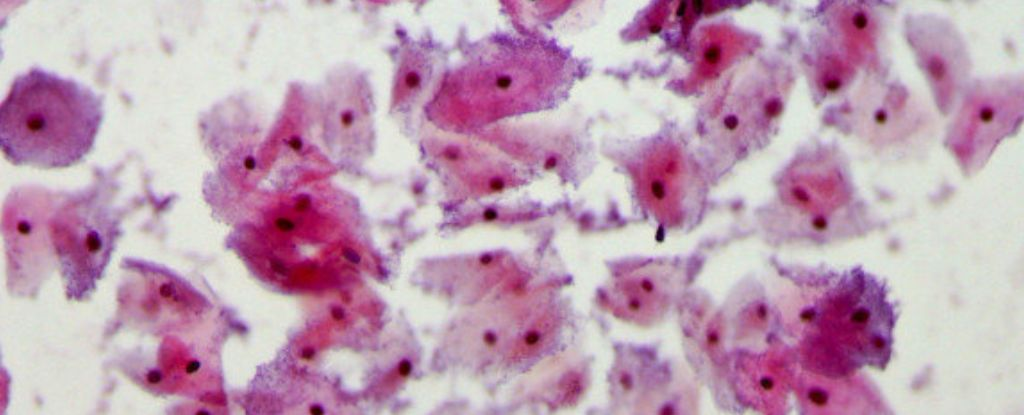

Бактеріальний вагіноз (БВ) — надзвичайно поширене захворювання, яке може виявитися недооціненою інфекцією, що передається статевим шляхом. При цьому стані порушується баланс вагінальної мікрофлори: шкідливі бактерії починають переважати над корисними. Це може викликати неприємний запах, незвичні виділення, свербіж або печіння, хоча в багатьох жінок симптоми відсутні. Досі вважалося, що БВ не є ІПСШ, оскільки бактерії походять із власного організму, однак нові дослідження ставлять це під сумнів.